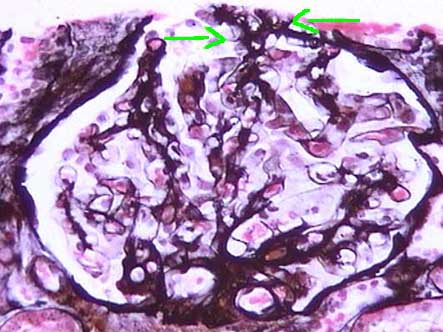

The characteristic histologic feature is sclerosis of segments of the glomerular tuft in some glomeruli (“segmental and focal”), with mesangial expansion and capillary lumen loss in these segments. The injury can be more notorious in the vascular pole or in the periphery of the tuft. When advancing the process the sclerosis becomes global and is indistinguishable of the secondary sclerosis to other diseases. The sclerosing segments are positive with PAS and silver-methenamine stains (type IV collagen). From the Fifties it is said that juxtamedullary glomeruli are more compromised by the segmental lesions. There are, in many cases, podocyte hypertrophy and hyperplasia, mainly on the surface of the sclerosed tuft segment (“cap lesion” or “cellular lesion”). Podocytes frequently appear with protein droplets and lipid resorption. The glomeruli without sclerosing lesions can appear normal or with increase of the mesangial cellularity and, sometimes, hypertrophic (glomerulomegaly).

Figure 2. With methenamine-silver stain the segments with loss of the capillary structure and sclerosis are better seen. The podocytes that cover these segments present hypertrophy and hyperplasia. (Methenamine-silver, X400).

Figure 5. The hyaline segments are negative with the methenamine-silver stain. The other segments show conserved capillary walls and mesangium. (Methenamine-silver, X400).